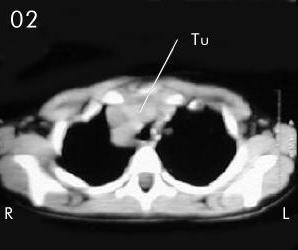

Tomografía torácica

Estudio Tomográfico tórax completo: En detalles los cortes progresivos desde el manubrio esternal hasta 2 cm sub carinal traqueal. (vistas desde el abdomen), (R) = derecho , (L) = Izquierdo; no se apreciaron procesos en pleura ni parenquima pulmonar.

En Mediastino antero superior:

Corte 01: Masa (Tu) densidad de partes blandas anterior lobulada con extensión lateral derecha de la traquea torácica.

Corte 02 y Corte 03: Se aprecia imagen de densidad de partes blandas en correlación con probable timo hiperplásico y/o timoma, extendiendose lateralmente a la derecha de la traquea con compresión y deformidad de la luz traqueal.